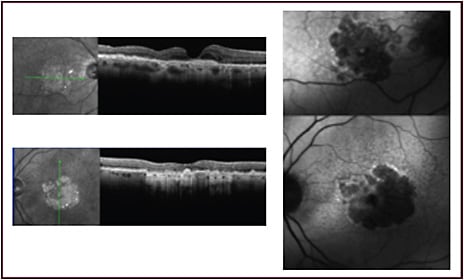

Dr Boyer: I get an OCT and OCTA, and look carefully for findings that will help me determine the cause of the patient’s visual complaints, considering that patients with AMD can have vision loss because of dry eye disease with multiple drusen or because of some other pathology, such as an epiretinal membrane. I also do fluorescein angiography if I suspect CNV or see hemorrhage. The fluorescein angiogram will not change my management for a patient with neovascular AMD, but it helps me detect a masquerade syndrome. I use indocyanine green angiography (ICGA) initially only if I suspect polypoidal choroidal vasculopathy (PCV) (Figure 1). Then, I use ICGA if a patient is not responding to anti-VEGF therapy.

Dr Boyer: I consider OCT to be a VEGF meter that gives me an idea of the response to anti-VEGF therapy, and I use it to look for a reduction of intraretinal and subretinal fluid. If the expected response does not occur after 3 to 4 injections, it is important to consider whether the condition is VEGF related or a masquerade syndrome, such as central serous chorioretinopathy, a drusenoid detachment, laminar drusen (Figure 2), polymorphous vitelliform maculopathy, optic pits, or polypoidal disease.